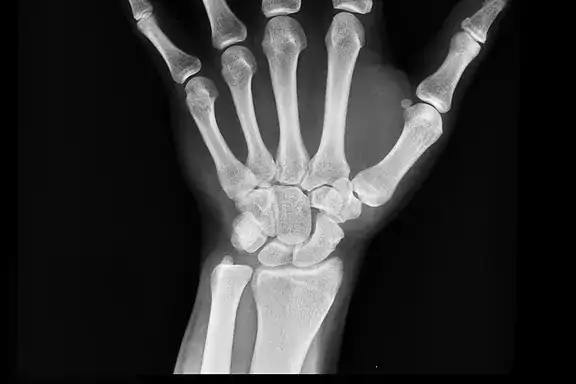

The radiography curriculum at A-B Tech prepares the graduate to be a radiographer, a skilled healthcare professional who uses radiation to produce images of the human body. Students admitted to the Associate Degree Radiography Program at A-B Tech must possess the capability to complete all aspects of the classroom and clinical curriculum. This curriculum requires demonstrated proficiency using a variety of cognitive, problem-solving, manipulative, communicative, and interpersonal skills. Therefore, all students in the program must possess the following abilities and meet the following expectations.

- Have sufficient use of the senses of vision, hearing, and touch necessary to directly perform a radiographic examination, review, and evaluate the dynamic images for the purpose of identifying normal and abnormal conditions.

- Learn and perform routine radiographic procedures, using the intellectual capacity to manipulate the x-ray tube according to the individual patient's needs and body habitus and the requirements of the procedure's standards of speed and accuracy.